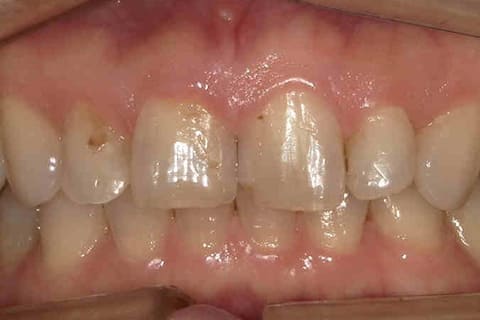

歯の色が気になる

Stain

他の歯と比べ色が黄色い。銀歯の部分が気になる。またもっと白い歯にしたいとお悩みの方へ

健康に美しく臨床実績集

虫歯や歯周病、事故などでの欠損、

噛めるようになりたい、見た目の美しさの追求など、

審美的に機能的に回復した治療経過報告症例です。